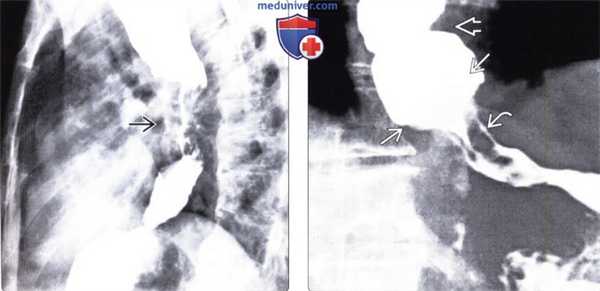

(Слева) На рентгенограмме пищевода, выполненной во время рентгеноскопии перед оперативным вмешательством — миотомией по Геллеру, определяются типичные признаки ахалазии в виде «птичьего клюва» в области дистального отдела пищевода, значительное расширение просвета вышележащих отделов пищевода, а также отсутствие перистальтических сокращений.

(Справа) На рентгенограмме пищевода у этого же пациента после миотомии по Геллеру определяется значительное уменьшение степени дилятации пищевода. Пищевод легко опорожняется в положении пациента стоя, его содержимое проходит в желудок под влиянием силы тяжести, т. к. перистальтика пищевода все еще отсутствует.

(Слева) На рентгенограмме пищевода определяются типичные признаки ахалазии, а также множественные бляшки неправильной формы, свидетельствующие о кандидозном эзофагите.

(Справа) На рентгенограмме пищевода со взвесью сульфата бария в вертикальном положении, полученной у женщины 78 лет с дисфагией, визуализируется не прошедшая в желудок пища и жидкость Ев на фоне выраженной дилятации просвета пищевода. Визуализируются также непропульсивные третичные сокращения пищевода. Этот пример является иллюстрацией гипертонической ахалазии, при которой стенка пищевода сокращается, но эти сокращения не являются эффективными. При манометрии была подтверждена ахалазия.

(Слева) На рентгенограмме пищевода, выполненной пациенту с длительно существующей ахалазией, визуализируется объемное образование, неравномерно суживающее просвет пищевода в виде «огрызка яблока». Позже было подтверждено, что образование представляет собой плоскоклеточный рак пищевода.

(Справа) На рентгенограмме определяется расширение просвета пищевода, а также третичные сокращения — изменения, напоминающие таковые при ахалазии. Резкое сужение просвета пищевода с «подрытыми» краями и наличие узловидно утолщенных складок слизистой оболочки позволяет заподозрить рак желудка, обусловливающий наличие признаков псевдоахалазии.